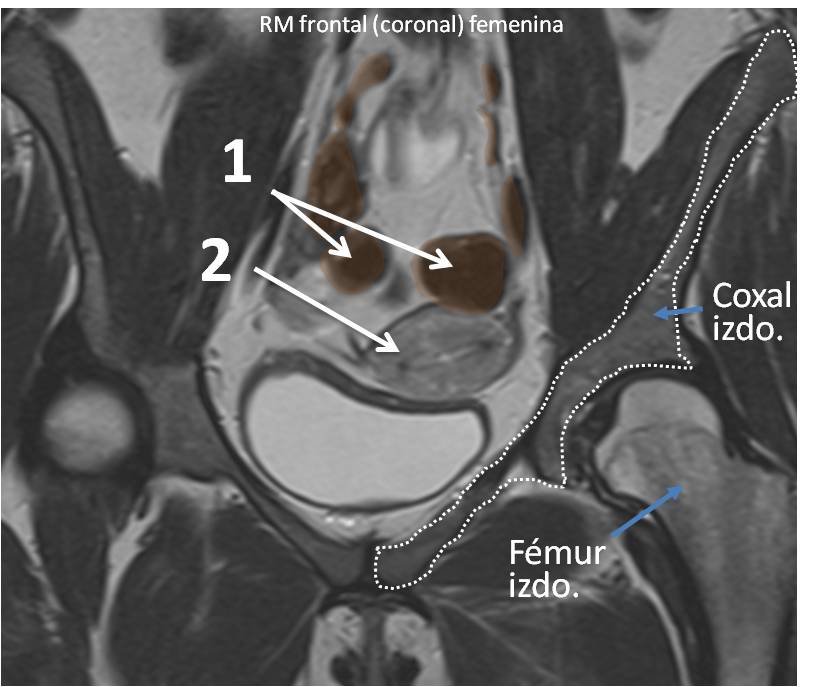

} Identifique las estructuras señaladas:

_Identifique las estructuras señaladas

" Identifique las estructuras señaladas

; Identifique las estructuras señaladas:

& Identifique las estructuras señaladas